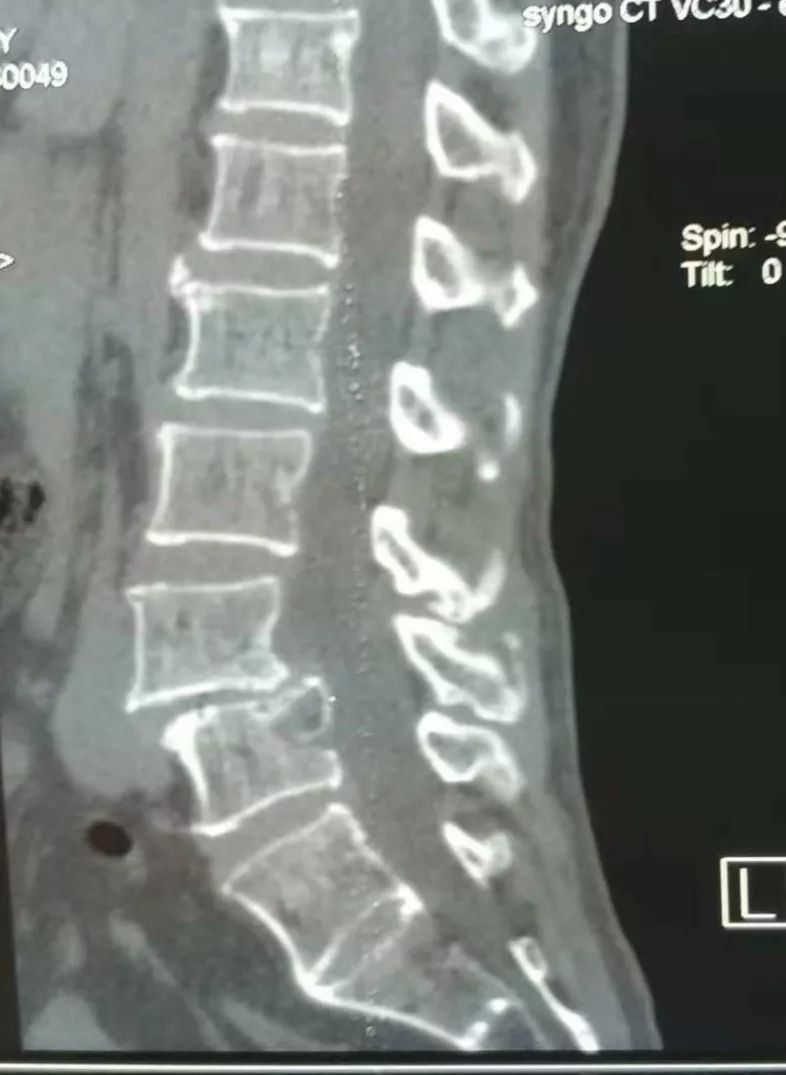

术前CT

术前CT提示腰4椎体向前滑脱,幅度超过椎体横径1/3,为II度滑脱。